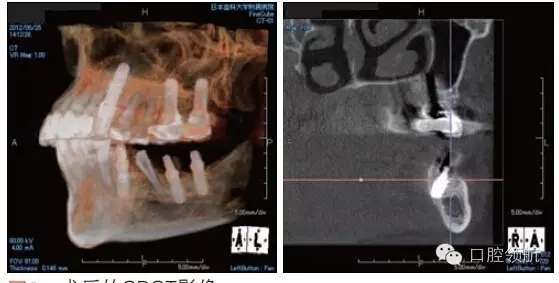

利用曲面斷層及CBCT檢查埋入部位情況,雖未出現(xiàn)與主訴相關(guān)的神經(jīng)損傷,但無意中卻發(fā)現(xiàn)了種植體的舌側(cè)穿孔(圖1、圖2)。

圖2 術(shù)后的CBCT影像。